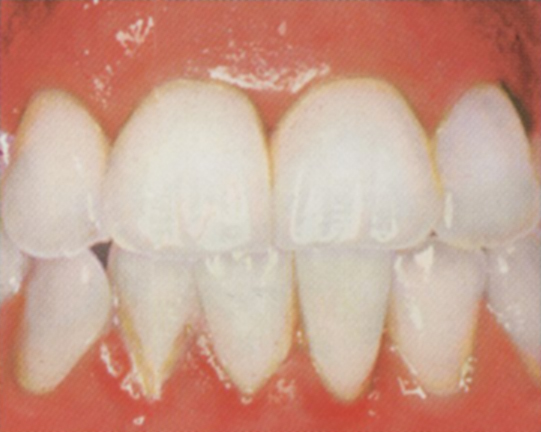

Healthy

- gums have healthy light pink colour

- gum line hugs teeth tightly

- no bleeding